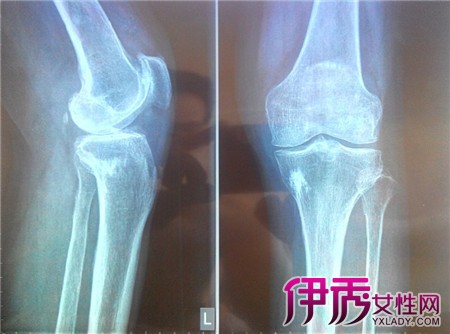

【图】膝关节滑膜炎的症状有什么 4种临床表现提醒患者

膝关节滑膜炎是一种无菌型炎症,是由于膝关节扭伤和多种关节内损伤而引起的。滑膜的功能异常会导致关节液无法正常生成和吸收,膝关节就会产生积液。滑膜的形态...

膝关节滑膜炎的症状